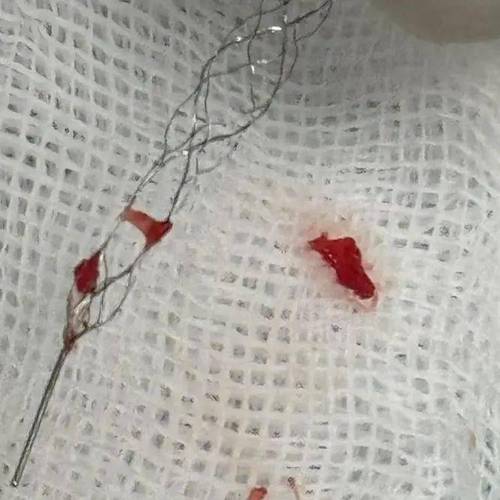

- 目的:在脑梗发生的急性期(通常6-24小时内),用于开通被血栓堵塞的大血管。

- 原理:医生通过导管将支架-like 的取栓装置送到血栓位置,抓住血栓并将其拉出体外,恢复血流。